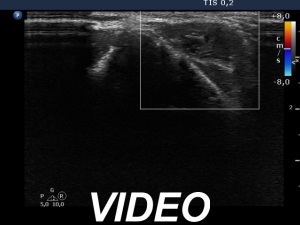

Ultrasonography. The right lobe remained unchanged. Compared with the previous finding, a much smaller, inhomogeneous mass was found according to the left lobe. A few centimeters above and ventral to the left lobe, a cystic lesion was found within the strap muscle and close to this, an amorphous hyperechoic fragment was also present (see video).